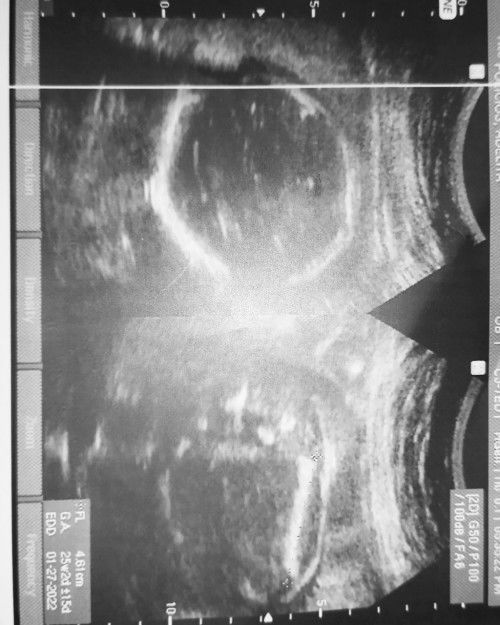

Hello mga momshies! Sino marungong bumasa ng ultrasound?😁 Ganito rin po ba pag baby GIRL?...

Baby Girl po yanπŸ₯°